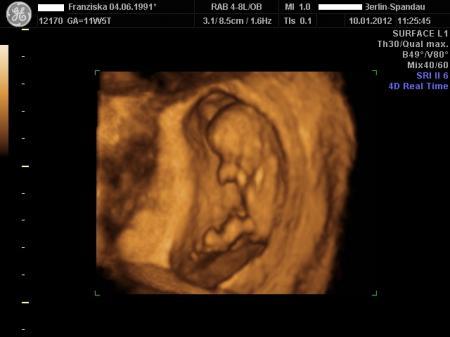

Habe gesehen das mein FA auf die DVD sogar ein 3D & ein 4D Bild getan hat, wollte euch mal das 4D Bild zeigen. Man erkennt das Baby zwar nicht prima, aber ich finds echt interessant wie es dort so allg aussieht! LG Franzi, die ab heute in der 13. SSW ist